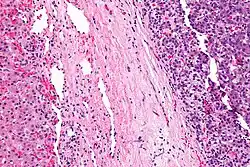

Micrograph of a hepatoblastoma. H&E stain. | |

Hepatoblastoma is a malignant liver cancer occurring in infants and children and composed of tissue resembling fetal liver cells, mature liver cells, or bile duct cells. They usually present with an abdominal mass. The disease is most commonly diagnosed during a child's first three years of life.[1] Alpha-fetoprotein (AFP) levels are commonly elevated, but when AFP is not elevated at diagnosis the prognosis is poor.[2]

Hepatoblastomas originate from immature liver precursor cells, are typically unifocal, affect the right lobe of the liver more often than the left lobe, and can metastasize. They are categorized into two types: "Epithelial Type" and "Mixed Epithelial / Mesenchymal Type."